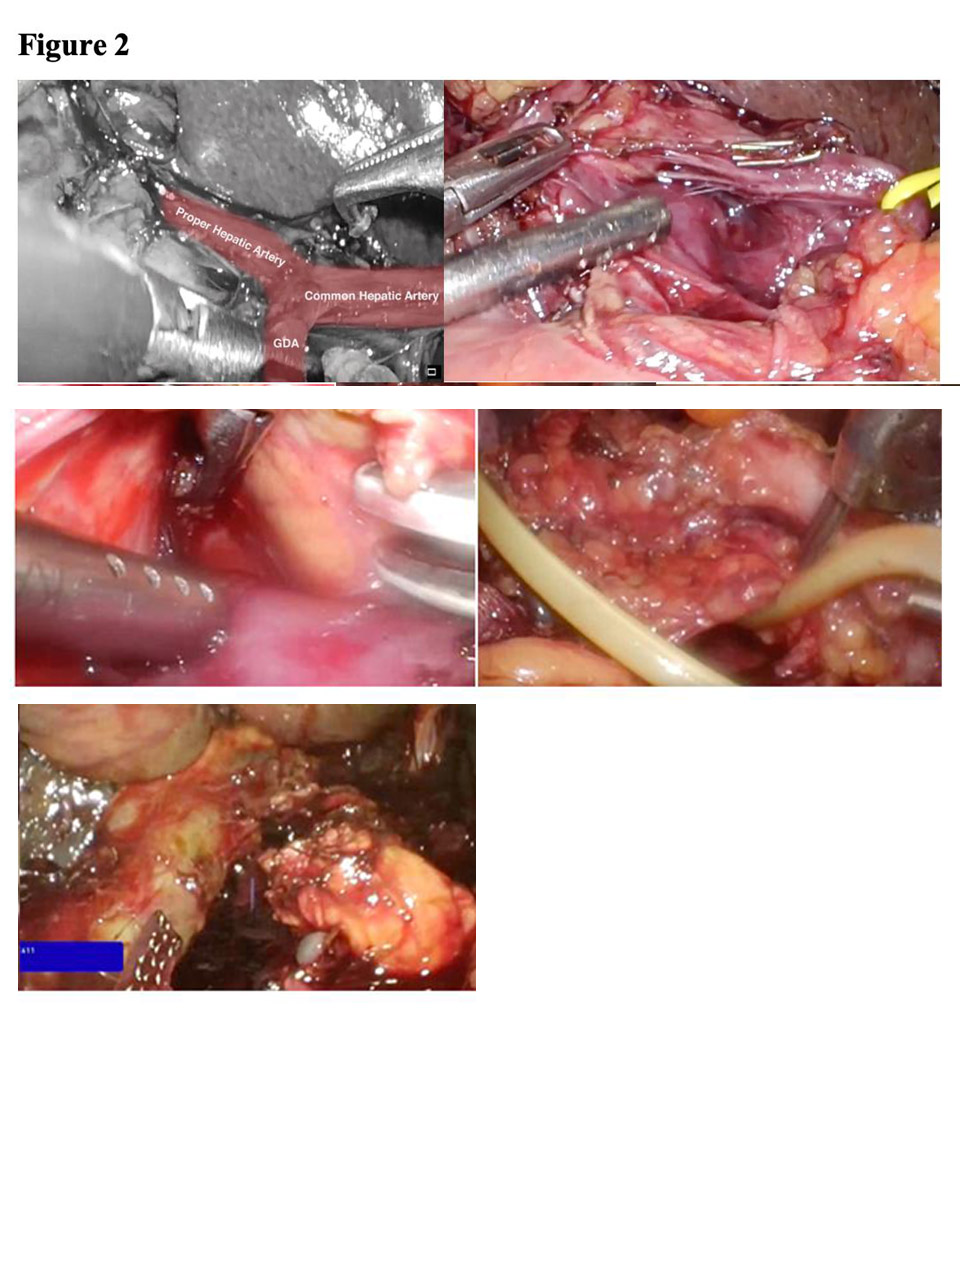

Diagram of Classical WhipplePancreatoduodenectomy is a formidable operation It involves removal of the head and uncinate process of the pancreas, the duodenum, the common bile duct and the gallbladder, with reconstruction by anastomosing the pancreatic remnant to the proximal jejunum or stomach, common hepatic duct to proximal jejunum and stomach or proximal duodenum to the jejunum.

The classical operation is called the Whipple resection, which includes removal of the distal stomach (gastric antrum and pylorus as well). These days we usually preserve the stomach and pylorus, the operation being called the pylorus-preserving proximal pancreatoduodenectomy (PPPPD).